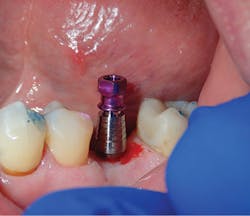

Being a network of small- to medium-sized private practice groups, we negotiated volume pricing on our favorite suite of manufacturer-direct systems. It is these systems that were uncovered during this process that we will highlight in the clinical portions of this series. We secured high-volume, manufacturer-direct, DSO-like pricing, and we call ourselves the Implant Alliance.In our practice of four dentists in Allen, Texas, we have been very intentional about making sure we can deliver incredibly high-quality dentistry at affordable rates for our patients. The case shown this month (figures 7–12; courtesy of Mike Dostal, DDS, FICOI) represents a very typical “I just need my tooth replaced” kind of day in our office. You see a patient in hygiene who has been missing a tooth for years and just didn’t want a bridge. Now, we can offer a simple appointment to place a flapless, sutureless implant, and the patient probably can go right back to work the same day.

The implant systems that satisfy this challenge the best for us are the iHex 1, 2, and 3 and MorsTorq systems by iH Biomedical. The iHex series is an internal hex that is compatible with most of the major internal hex systems. It incorporates platform switching, which allows for crestal or subcrestal placement. The designers created a multicompatibility surgical kit that minimizes the number of drills (often just one needed) used to place and restore the implants. The platforms are the same across most sizes, which reduces the number of abutments that must be stocked. Also, the implant, abutment, and cover screw are all included. These design features place this system at the top of the list when it comes to economics and excellence rolled into one package.